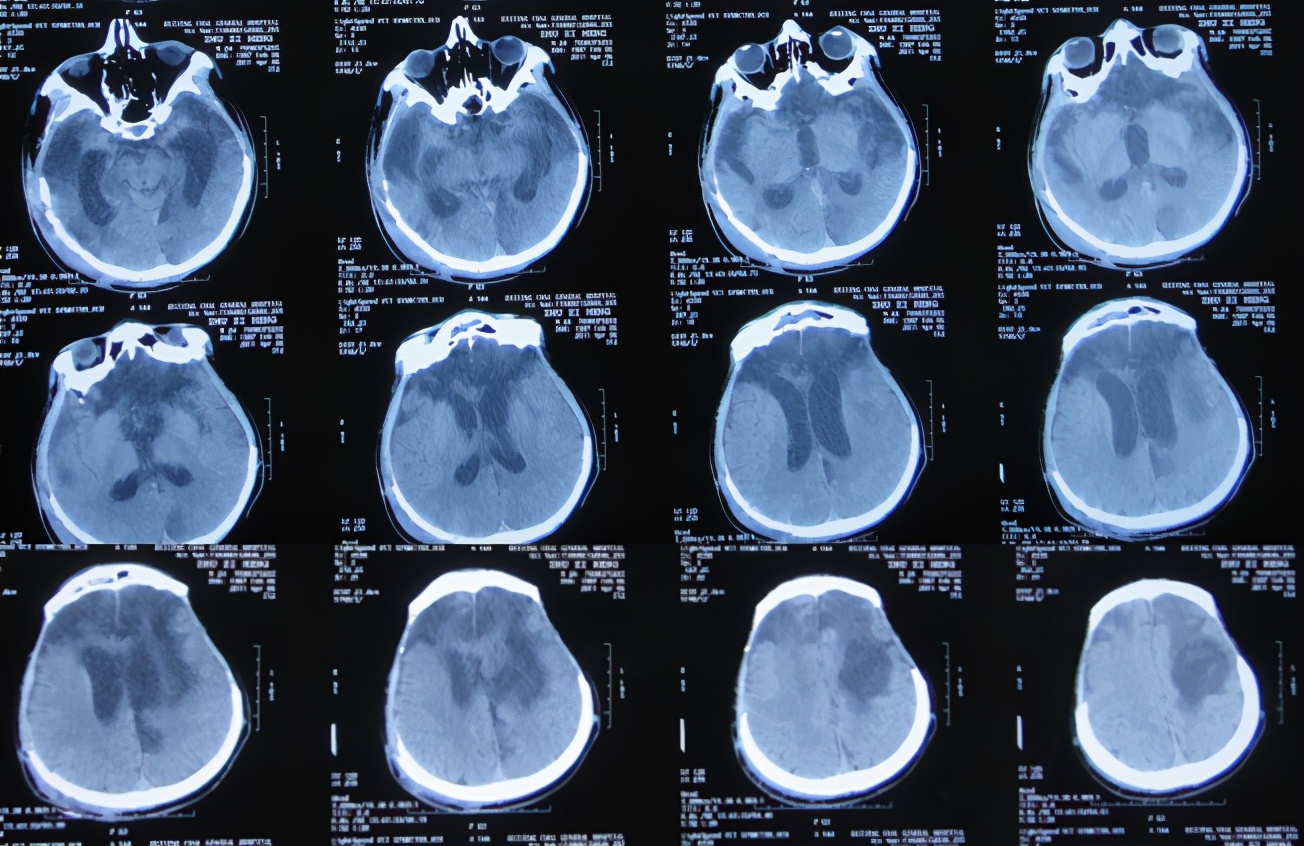

随后立即给予腰大池引流和抗感染治疗,27天后即2011年5月27日(干细胞移植治疗31天后即开颅术后132天),患者病情反而更加重,意识变差,仍间断发热;查头颅CT示仍脑积水和水肿变得更加严重( 图-5 ),因此不得不转入该院的重症监护室。

图-5: 2011年5月27日头颅CT

重症监护室治疗20天即2011年6月16日(干细胞移植治疗51天后即开颅术后152天),患者意识稍有好转,体温也变为正常;查头颅CT示脑积水仍未见改善( 图-6 ),所以转回普通病房。

图-6: 2011年6月16日头颅CT